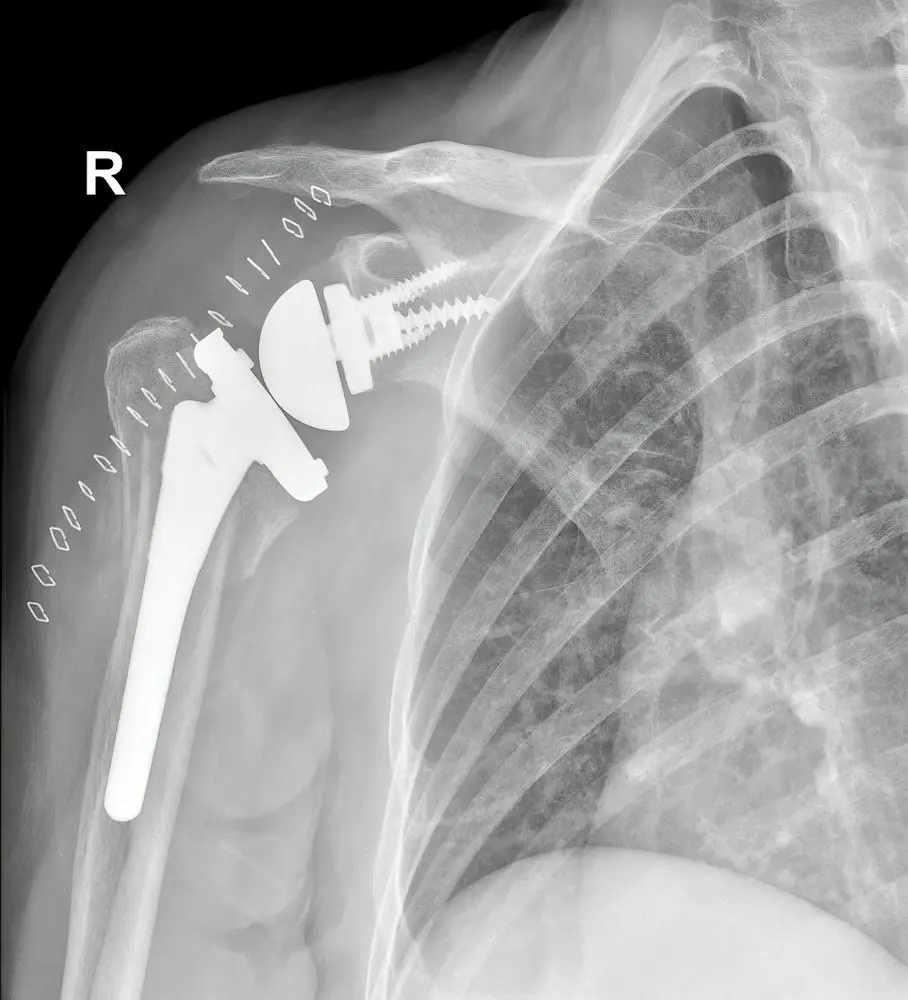

To understand reverse shoulder replacement, it helps to first understand how a normal shoulder works. The shoulder is a ball-and-socket joint, where the ball (the head of the humerus) fits into a shallow socket (the glenoid). In a traditional shoulder replacement, the damaged ball is replaced with a metal ball, and the socket is resurfaced with a plastic component to maintain the joint’s natural structure.

Reverse shoulder replacement, however, literally “reverses” the anatomy of the joint. The ball component is attached to the shoulder blade, and the socket component is attached to the upper arm bone.

In a healthy shoulder, the rotator cuff muscles help stabilize and move the joint. But when the rotator cuff is severely torn or nonfunctional, a traditional replacement may not restore stability or motion. By reversing the ball-and-socket configuration, the mechanics of the shoulder shift so that the deltoid muscle (a larger, stronger muscle) takes over much of the lifting function.

This innovative design allows patients with rotator cuff deficiency to regain improved shoulder elevation, stability, and pain relief, even when traditional surgery would not be effective.